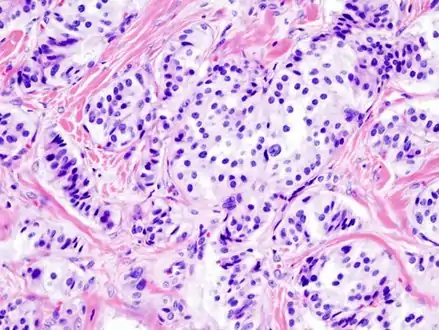

Pancreatic insulinoma